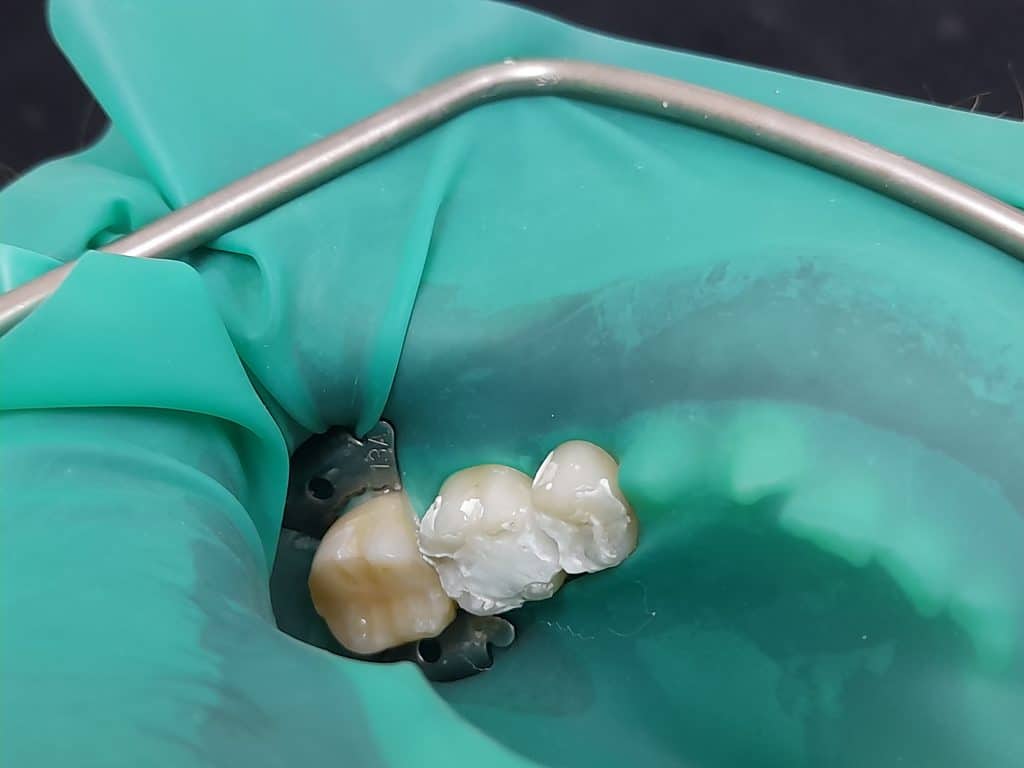

1.1st session: vital pulp therapy, neoputty. tooth 35

Root canal treatment, lateral condensation obturation, resin based sealer. Tooth 36

2. 2nd session: Composite build up, layering technique, tokoyama estellite conventional and bulk fill.